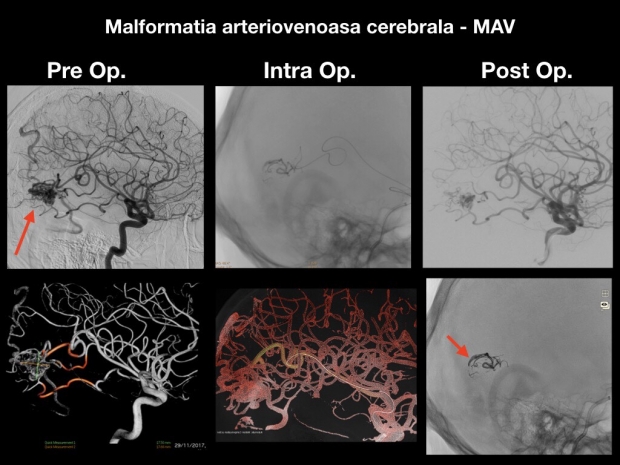

Cele mai multe cazuri de intervenţii minim invazive se referă la patologii dificile de trat în mod clasic, cum ar fi anevrismele cerebrale, accidentele vasculare ischemice sau stenoza cartodiană. De pildă, anevrismul cerebral beneficiază de o rată de succes impresionantă prin această tehnică.